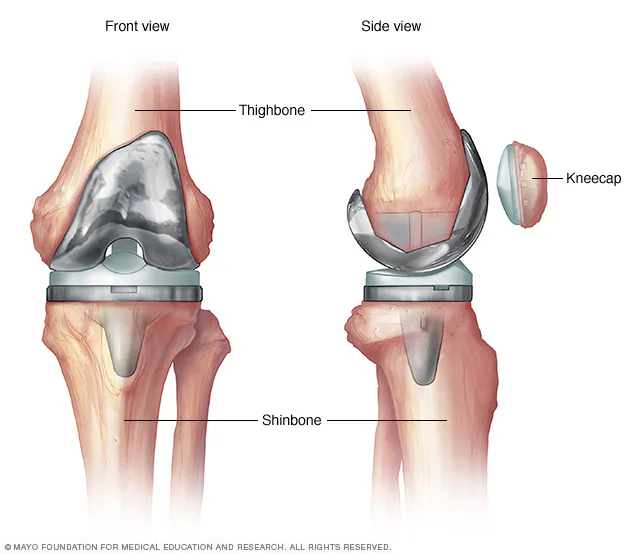

Total Knee Replacement (TKR)

Total Knee Replacement is a surgery where damaged knee joint surfaces are replaced with high-grade metal and polyethylene implants to relieve pain and restore function.